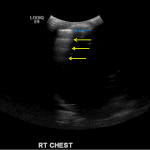

- No right pleural fluid collection identified

Large, complex, multiseptated left pleural fluid collection with adjacent airspace consolidation, concerning for pneumonia and empyema. No discernible right pleural effusion.

- Normal, air-filled lung looks like television static on ultrasound. What you CAN see is the pleural lining, which will appear as a hyperechoic line with multiple parallel reverberations of that line extending deep into the lung like ripples – these are called “A-lines” (see annotated image #2)